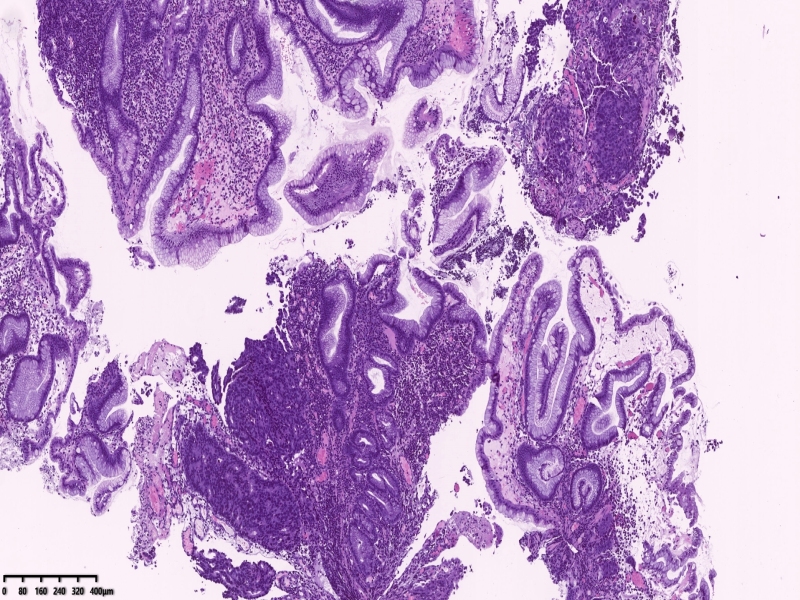

胃镜可见距离门齿35厘米一下可见一肿物凸向管腔,向下延伸至贲门口、胃体上部,管腔狭窄,胃镜勉强通过,肿物中央城溃疡状,覆盖白苔,周围坎坝杨改变,活检8块。

镜下所见:胃粘膜组织数块,炎症背景,其中3块固有层内可见细胞团,瘤细胞排列呈条索状迂回后呈巢状,巢的边缘瘤细胞呈栅栏状。细胞形态似柱状。